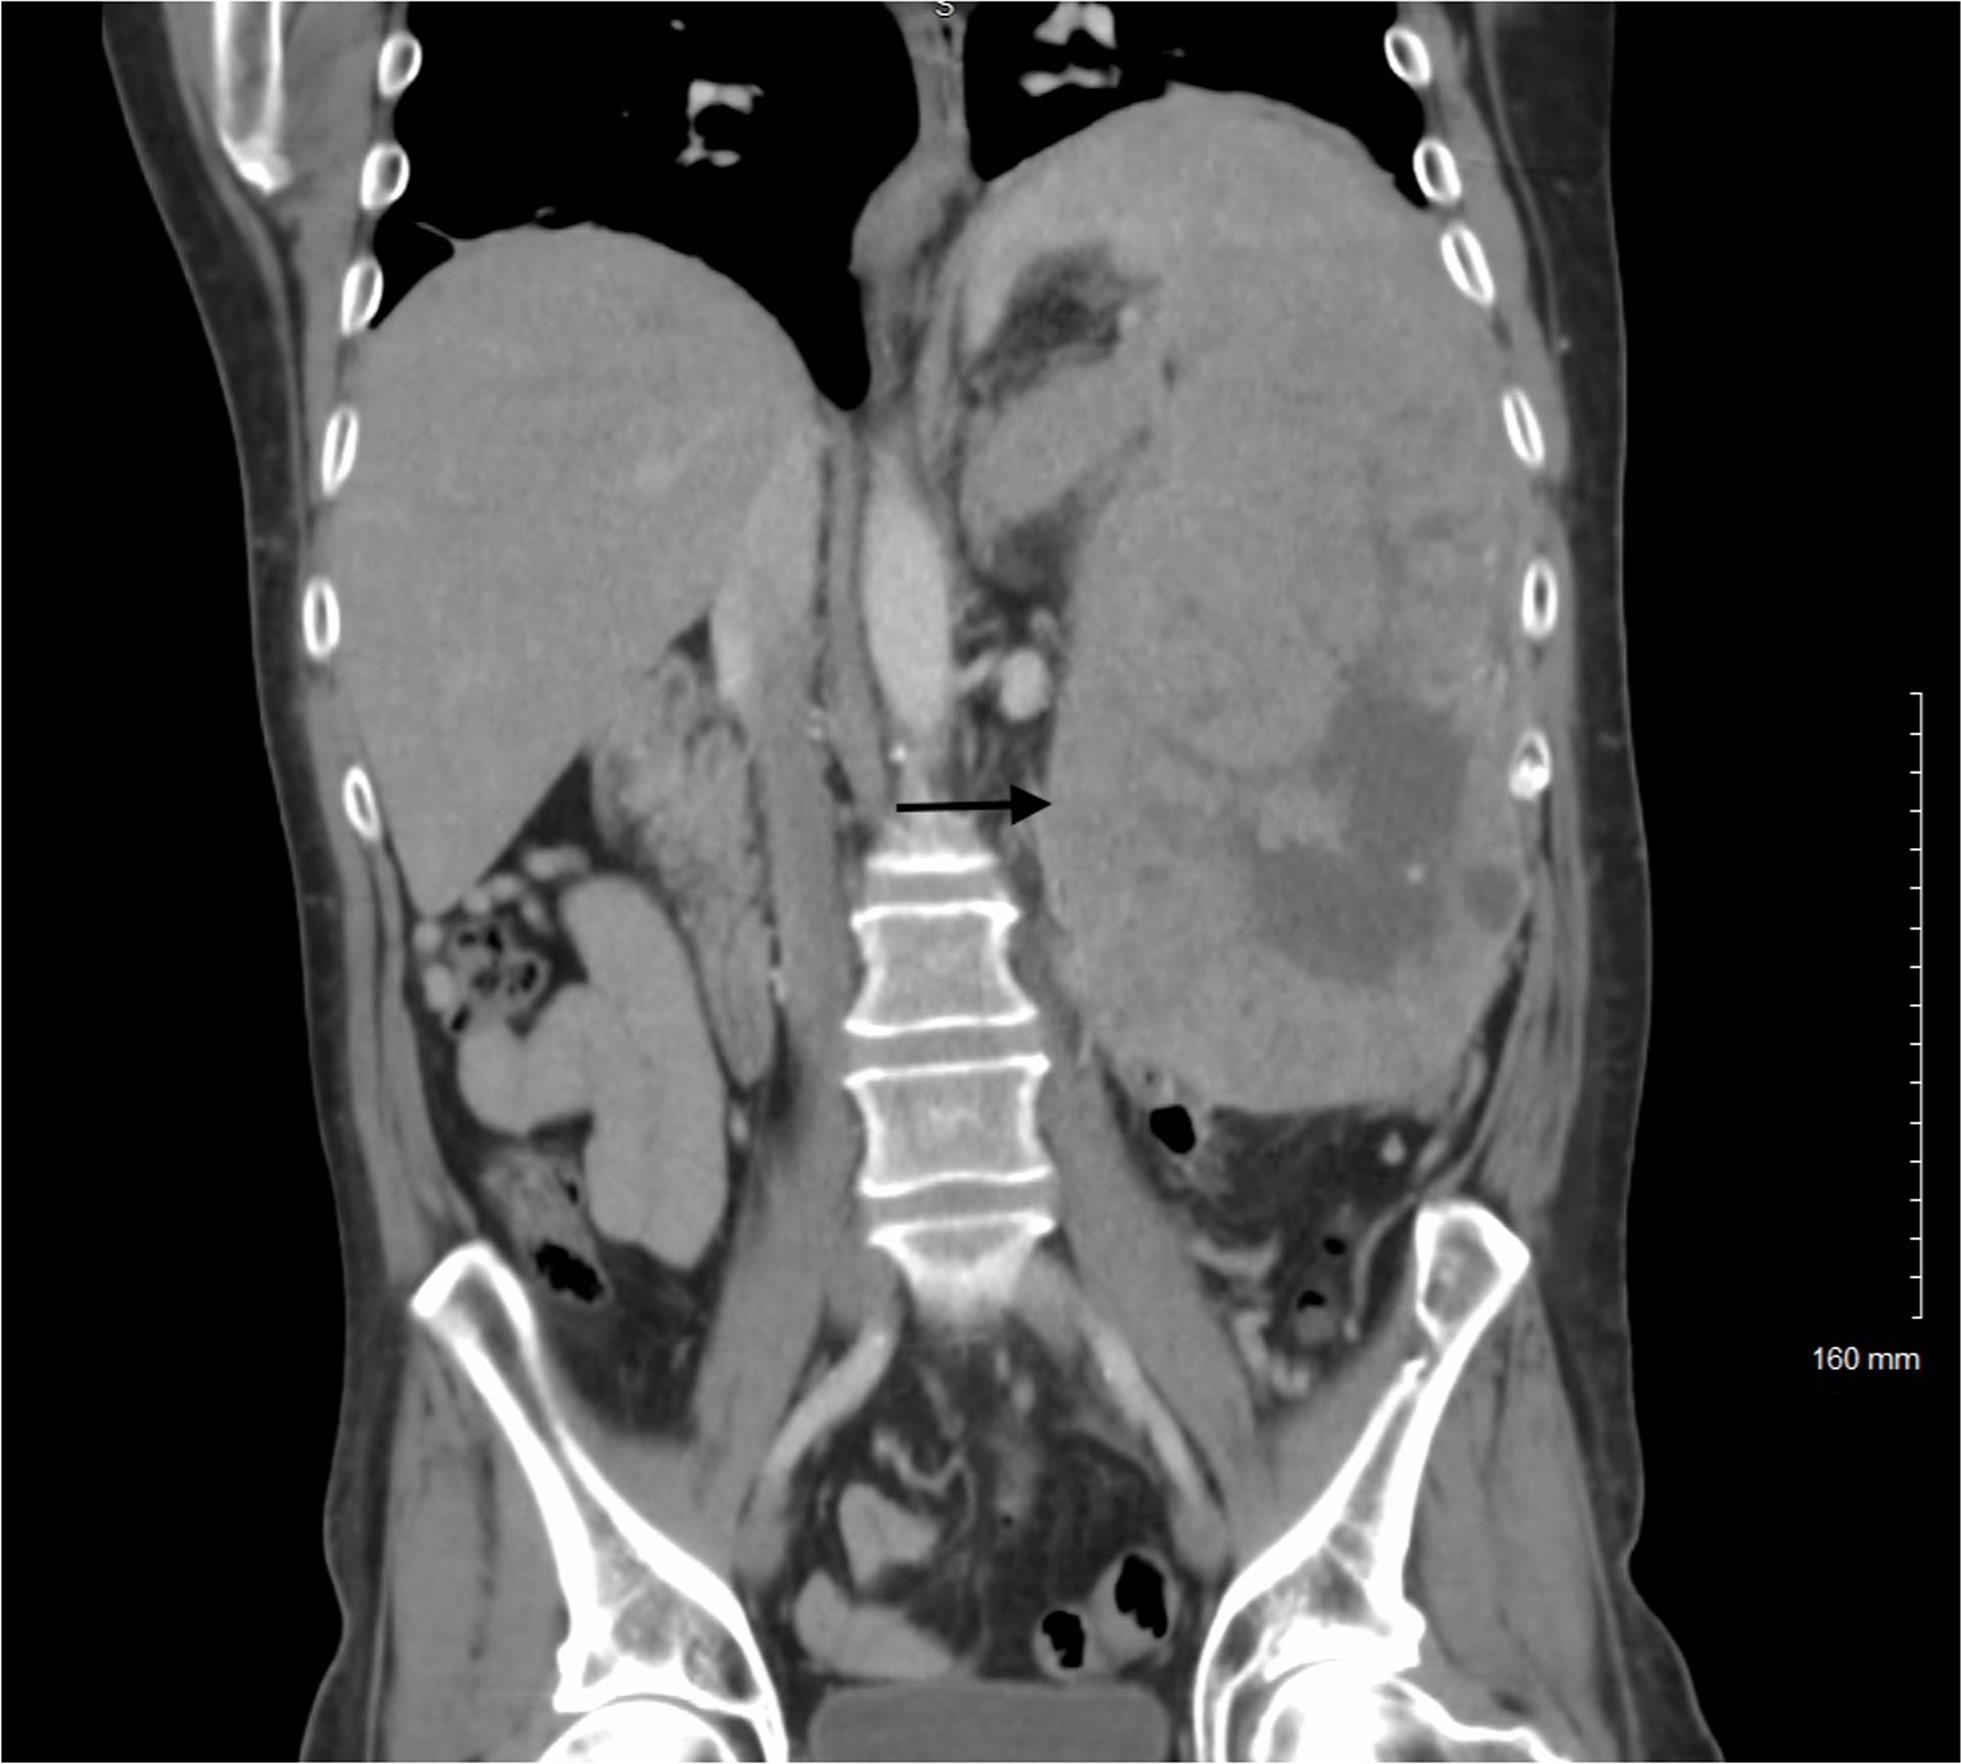

A 48-year-old man presented with a 7-month history of progressive abdominal pain, distention, and weight loss. His family history included colon cancer in his father, Müllerian cancers in his mother and maternal grandmother, and breast cancer in a maternal aunt diagnosed at age 32. Computed tomography imaging revealed a 22-centimeter, heterogeneous splenic mass with central necrosis (Fig. 1), thought to most likely represent a primary splenic angiosarcoma. No radiologic abnormality was identified in the pancreas. His serum level of alpha-fetoprotein was 109 ng/mL (reference range ≤8 ng/mL).

Computed tomography imaging shows a 22-centimeter, heterogeneous splenic mass with central necrosis.

Fig. 1  Computed tomography imaging shows a 22-centimeter, heterogeneous splenic mass with central necrosis.